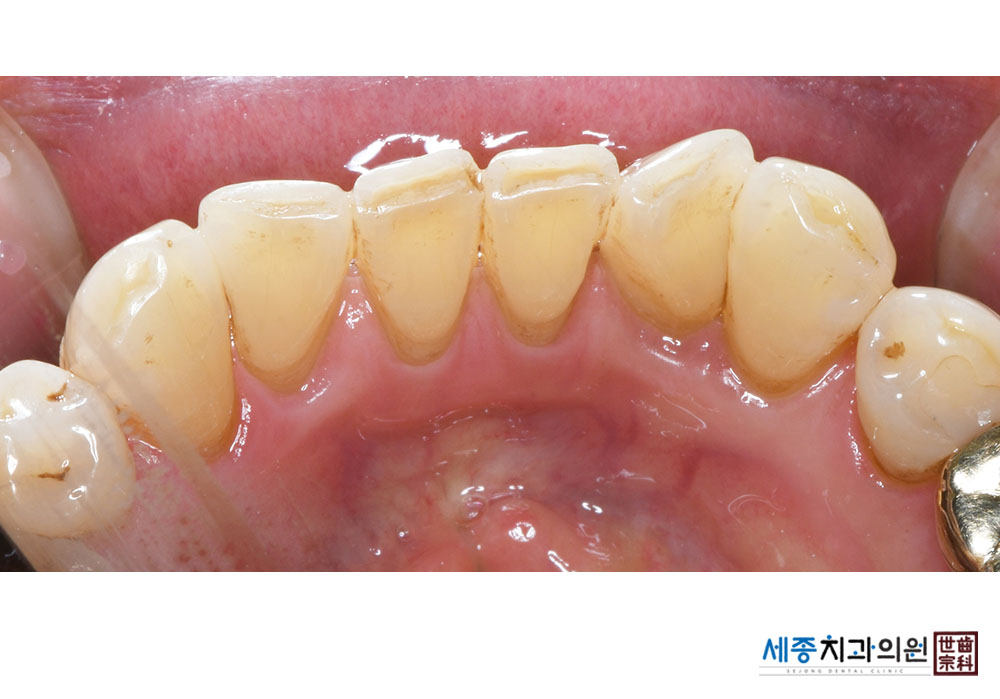

[스케일링] 치주질환 예방 스케일링

치료전 : 2023-02-13

가글마취&저주파 스켈러를 사용한 스케일링